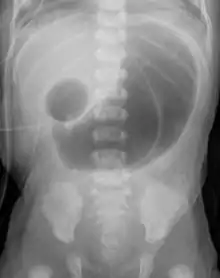

Radiograph with double bubble sign indicating duodenal atresia | |

If not diagnosed in utero, infants with intestinal atresia are typically diagnosed at day 1 or day 2 after presenting with eating problems, vomiting, and/or failure to have a bowel movement.[3] Diagnosis can be confirmed with an X-ray, and typically followed with an upper gastrointestinal series, lower gastrointestinal series, and ultrasound.[5][3]